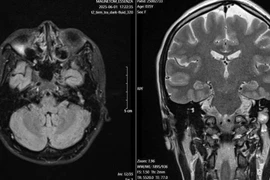

Hội chứng gương là bệnh lý sản khoa hiếm gặp, để chỉ tình trạng phù toàn thân của người mẹ “phản chiếu” tình trạng phù của thai nhi.

Các bác sĩ Bệnh viện Sản nhi Bắc Ninh Số 1 đã phẫu thuật cấp cứu và điều trị, hồi sức thành công cho bệnh nhân Ngô Thị Luyến nhập viện trong tình trạng phù toàn thân, khó thở, tăng huyết áp, tràn dịch đa màng, phù phổi có nguy cơ phù phổi cấp (trước, trong và sau mổ) do biến chứng của Hội chứng gương (Mirror Syndrome) gây ra.

Đây là một căn bệnh đặc biệt nguy hiểm và hiếm gặp trong thai kỳ được ghi nhận lần đầu tiên tại Bệnh viện Sản nhi Bắc Ninh Số 1.